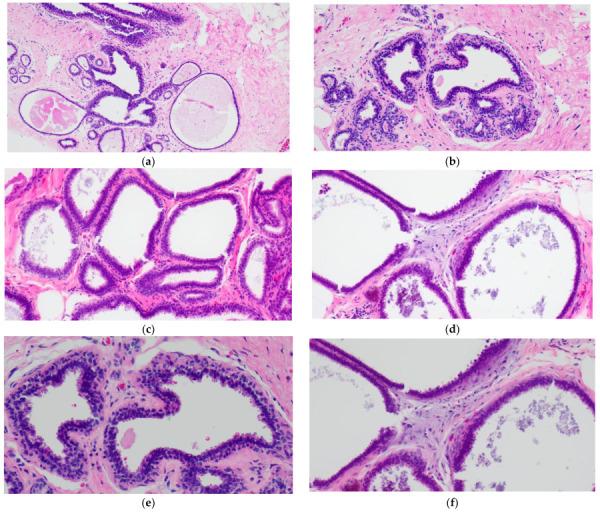

Columnar cell lesions (CCLs) of the breast comprise a spectrum of morphologic alterations of the terminal duct lobular unit involving variably dilated and enlarged acini lined by columnar epithelial cells. The World Health Organization currently classifies CCLs without atypia as columnar cell change (CCC) and columnar cell hyperplasia (CCH), whereas flat epithelial atypia (FEA) is a unifying term encompassing both CCC and CCH with cytologic atypia. CCLs have been increasingly recognized in stereotactic core needle biopsies (CNBs) performed for the assessment of calcifications. CCLs are believed to represent the earliest non-obligate precursor of low-grade invasive breast carcinomas as they share molecular alterations and often coexist with entities in the low-grade breast neoplasia pathway. Despite this association, however, the risk of progression of CCLs to invasive breast carcinoma appears low and may not exceed that of concurrent proliferative lesions. As the reported upgrade rates of pure CCL/FEA when identified as the most advanced high-risk lesion on CNB vary widely, the management of FEA diagnosed on CNB remains controversial. This review will include a historical overview of CCLs and will examine histologic diagnostic criteria, molecular alterations, prognosis and issues related to upgrade rates and clinical management.

乳腺柱状细胞病变(CCL)是一种累及终末导管小叶单位的形态学改变,包括各种程度的扩张和增大的腺泡,由柱状上皮细胞排列而成。目前,世界卫生组织将无异型的 CCL 分为柱状细胞改变(CCC)和柱状细胞增生(CCH),而扁平上皮异型性(FEA)是一个统一的术语,包括伴有细胞学异型性的 CCC 和 CCH。CCL 在用于评估钙化的立体定向核心针活检(CNB)中越来越被认识。CCL 被认为是低级别浸润性乳腺癌的最早非必需前体,因为它们具有分子改变,并且经常与低级别乳腺肿瘤途径中的实体共存。然而,尽管存在这种关联,但 CCL 进展为浸润性乳腺癌的风险似乎较低,并且可能不会超过同时存在的增生性病变的风险。由于在 CNB 上被确定为最高危病变时,纯 CCL/FEA 的报告升级率差异很大,因此在 CNB 上诊断出的 FEA 的管理仍然存在争议。这篇综述将包括 CCL 的历史概述,并将检查组织学诊断标准、分子改变、预后以及与升级率和临床管理相关的问题。